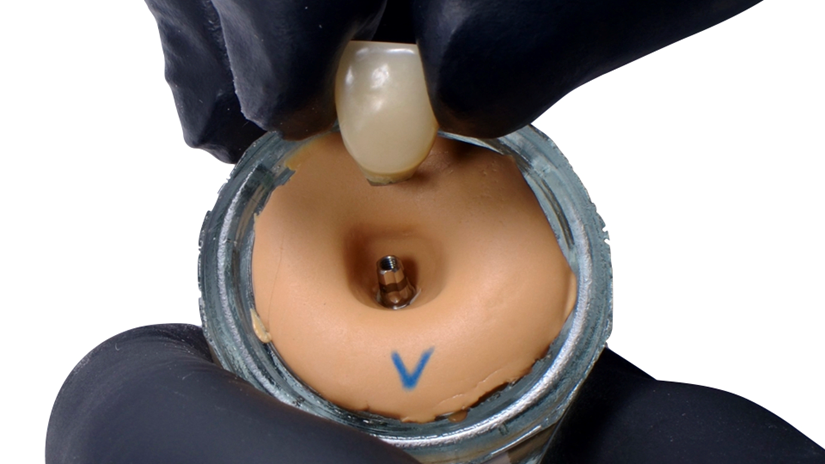

A paciente apresentava queixas estéticas e funcionais. Após avaliação clínica e radiográfica, optou-se pela substituição do pilar reto por um pilar Ideale angulado de 17 graus e 3,3 mm de diâmetro. Esse componente mais estreito e angulado permitiu corrigir o eixo emergente da futura coroa, viabilizando o planejamento de uma prótese parafusada na região estética.

O caso foi conduzido com planejamento cuidadoso, moldagens analógicas e provas clínicas. A reabilitação foi finalizada com a instalação de uma coroa metalocerâmica parafusada, garantindo estética, funcionalidade e reversibilidade do conjunto protético.

Esse protocolo evidencia como a seleção correta do pilar protético, respeitando angulação e diâmetro adequados, pode contornar limitações anatômicas e transformar um caso potencialmente desfavorável em um resultado previsível e satisfatório.